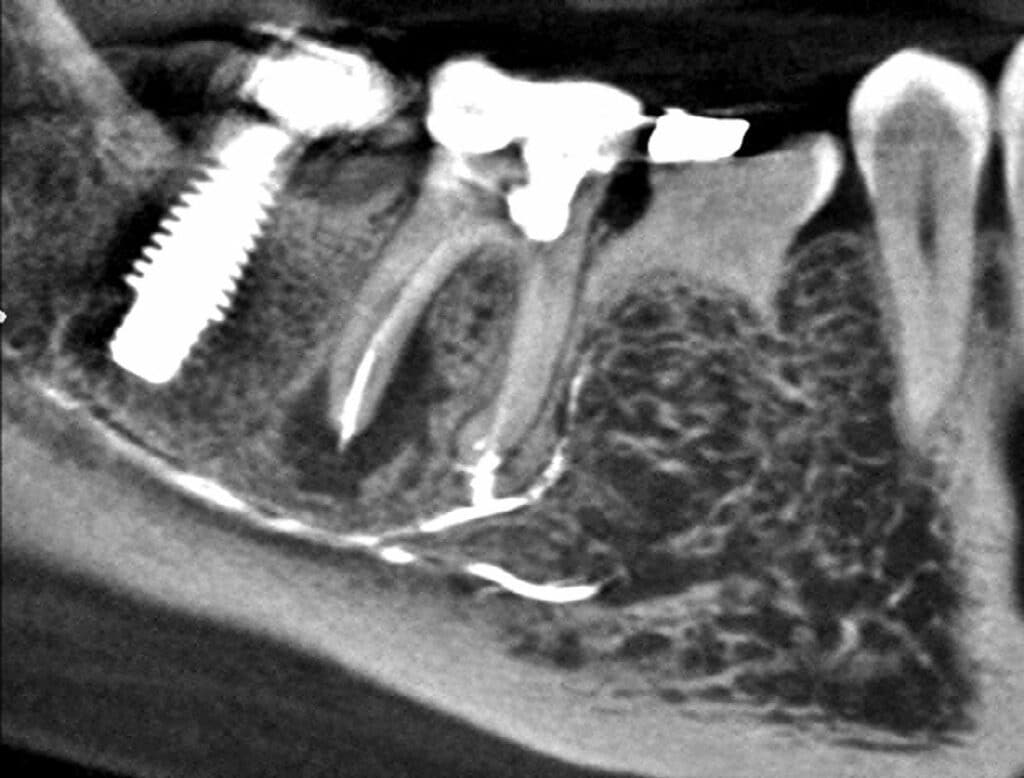

Calcium Silicatebased Sealer Extrusion into the Mandibular Canal 3 Sealer Extrusion Endodontics — therefore, the present study was intended to evaluate cases of unintentional overfillings after using different sealers for the fate of the. This study aimed to investigate the effect of unintentional ah plus sealer extrusion on the outcome of. — the quality of filling is closely related to endodontic success. Treatment outcome was not significantly. — periapical. Sealer Extrusion Endodontics.

Calcium Silicatebased Sealer Extrusion into the Mandibular Canal 3 Sealer Extrusion Endodontics not all extruded sealers were predictably removed from the periradicular tissues. — therefore, the present study was intended to evaluate cases of unintentional overfillings after using different sealers for the fate of the. The optimal obturation is achieved by densely sealing. — the quality of filling is closely related to endodontic success. — periapical lesions showed. Sealer Extrusion Endodontics.